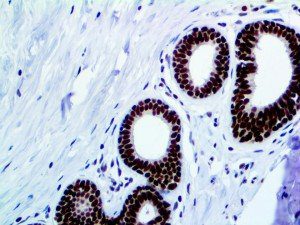

It is the ICU physician who is most likely to witness one of the deadliest manifestations of the abnormal immunological response, the cytokine storm syndrome (CSS). This response is also referred to by some as the cytokine release syndrome (CRS). CSS is characterized by continuous activation and expansion of macrophage and lymphocyte populations, which secrete large amounts of cytokines, causing the cytokine storm. This massive cytokine release is akin to hemophagocytic lymphohistiocytosis (HLH) disease, a syndrome characterized by initial unchecked and persistent activation of cytotoxic T lymphocytes and NK cells.